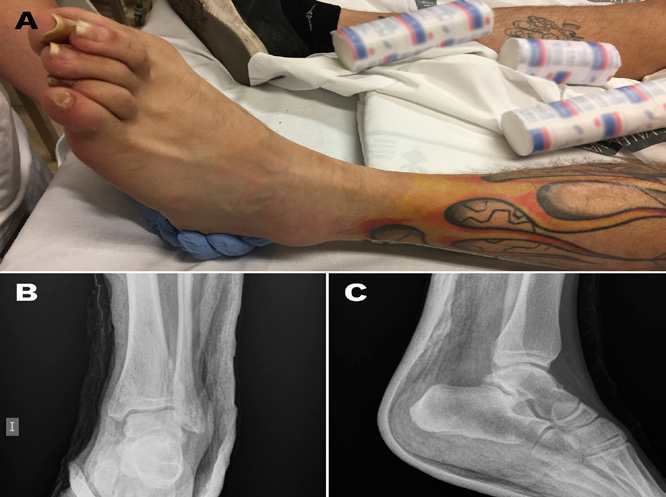

At the 6-month follow up, the patient achieved a score of 99 points in the questionnaire of the American Orthopedic Foot and Ankle Society (AOFAS).4 and had resumed sport activity without clinical repercussion (Figure 4).

Figure 4A ankle movement at the 6-month follow up; B: conventional X-Ray (B, anteroposterior view; C, lateral view) showing correct joint congruence and absence of chronic bone lesions.